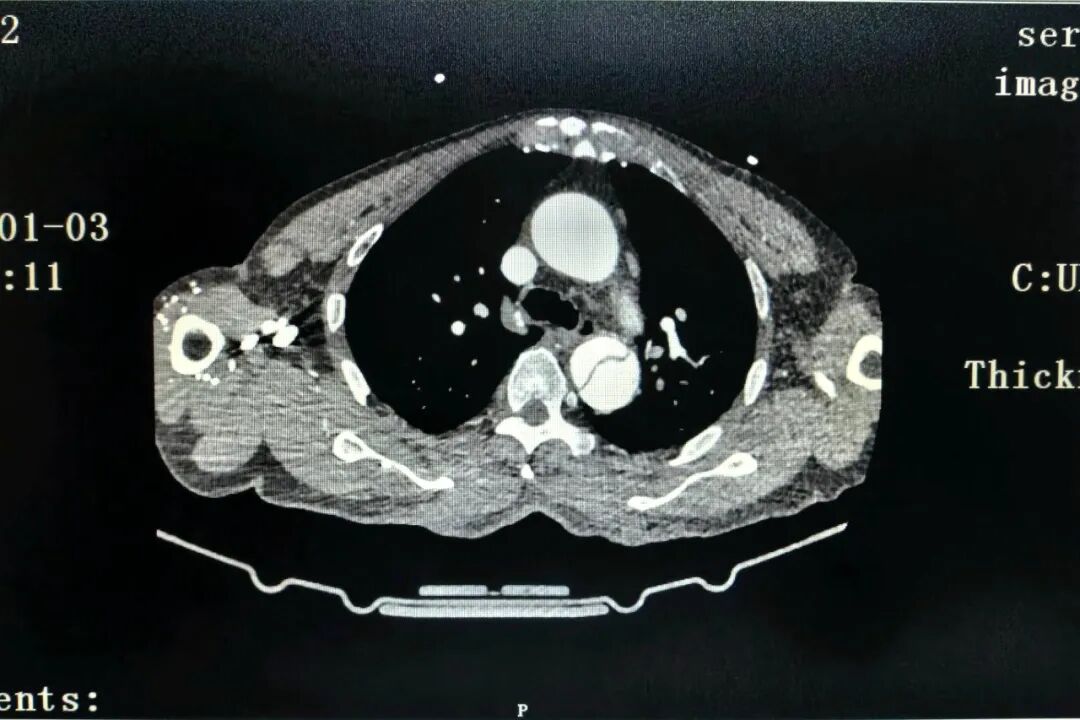

据了解,该名患者为老年男性,既往有慢性胃炎、高血压病史,于2026年1月3日无明显诱因突发胸痛,以胸骨中下段为甚,呈剧烈疼痛,伴大汗淋漓、烦躁不安及恶心症状,持续数分钟无法自行缓解,遂来医院就诊。入院后急诊完成首份心电图检查,提示“窦性心动过缓,ST-T段改变”,考虑到患者症状凶险,为其进行急诊CTA检查,最终确诊为:主动脉夹层(DeBakey Ⅲ型,Stanford B型),高血压危象。给予控制血压、止痛等积极抢救处理后,患者被转入心血管内科进一步治疗。

图片图片

(术前CT造影)